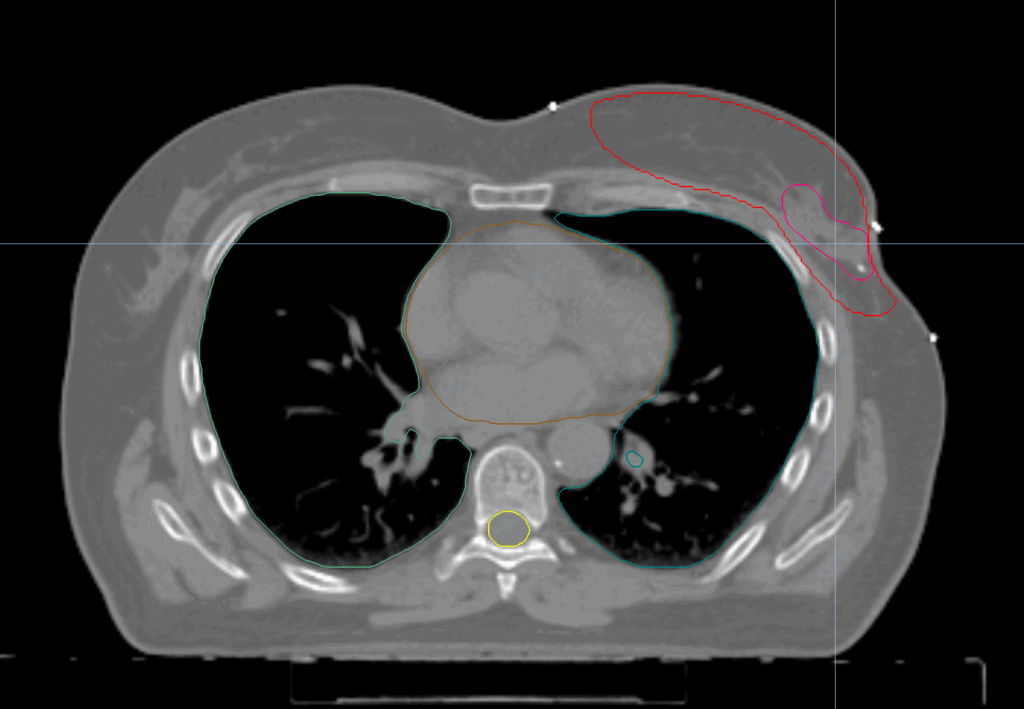

Complex Left Breast SIB and Nodes

< View All Plan Studies RADIXACT SYSTEM Complex Left Breast SIB and Nodes Case History AGE: 76-year-oldGENDER: Male Medical History Immidiate tolerance: Grade II dermatitis with eyelid edema, Grade I conjunctivitis resolved with Sterdex Diagnosis: Squamous cell carcinoma of the right lower eyelid Planning CT Images Treatment Plan Images ClearRT® Images Treatment Planning Highlights Fractionation […]